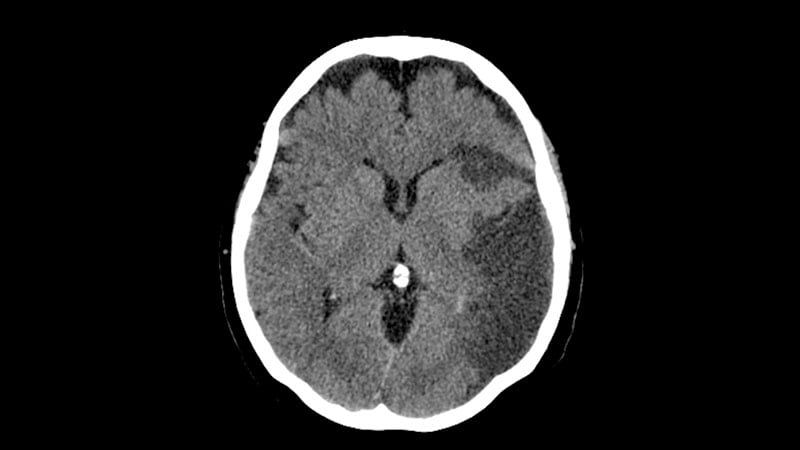

More Support for Thrombectomy in Large Core StrokeA new study and a meta-analysis provide more evidence that patients with large ischemic strokes and a significant amount of

brain tissue damage may still benefit from thrombectomy.